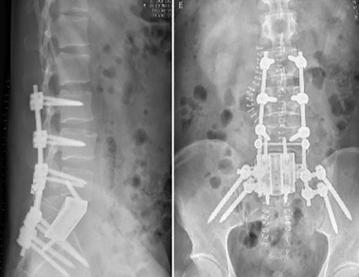

手術(shù)在新的一天的凌晨2點結(jié)束,術(shù)中跟臺護士更換了3批,患者翻身2次,歷時10余個小時,生命體征未出現(xiàn)波動,患者在ICU病房幾小時后即拔管蘇醒。術(shù)后的患者如廁正常,并已下地活動,復查X光片,內(nèi)固定位置良好,假體完全貼合。